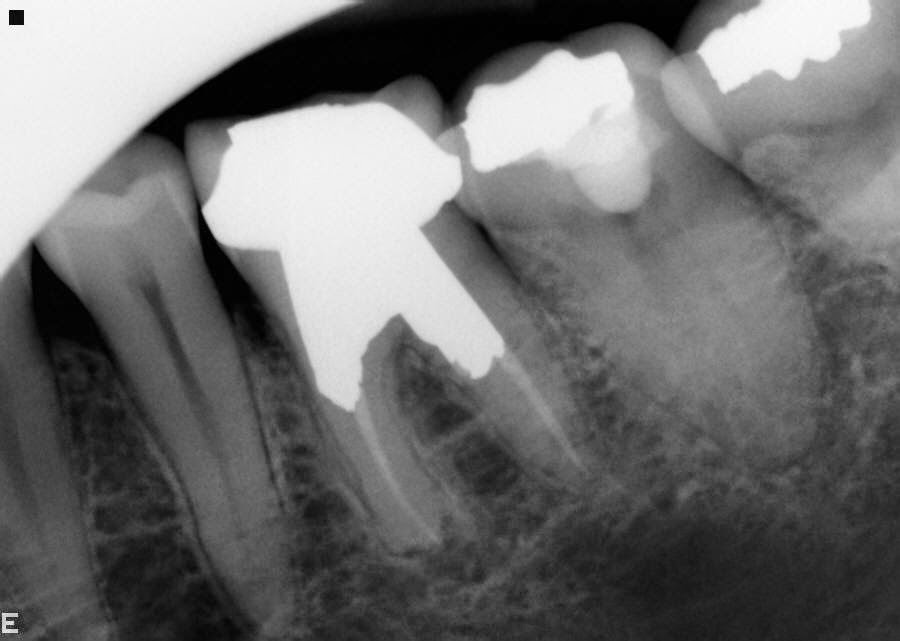

The telltale signs of failed root canal with Xray pictures Failed Root Canal Under Crown Web a new crown will need to be put on in this case, it needs to bind tightly to the tooth to do its job properly. Web dental crowns can crack, or the inner seal used to fill the canal might start to erode. In these scenarios, or if the tooth suffers a trauma, bacteria can be reintroduced into the. Failed Root Canal Under Crown.